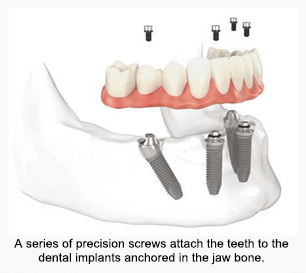

Teeth-in-a-Day and All-on-4® Dental Implants

The All-on-4® treatment concept is a state-of-the-art innovative procedure that provides patients permanent attached (fixed) teeth utilizing as few as four dental implants. We offer you new teeth in as little as one day by using the All-on-4® treatment concept for those that are about to lose or have lost all their upper and/or lower teeth.

- Benefits of Permanent Teeth in 1 Day

- New teeth in as little as just one day

- Minimally invasive procedure

- No more ill-fitting dentures

- Eliminates denture adhesives

- Teeth are secure like your natural teeth

- Cost effective compared to traditional implants

- Life changing procedure